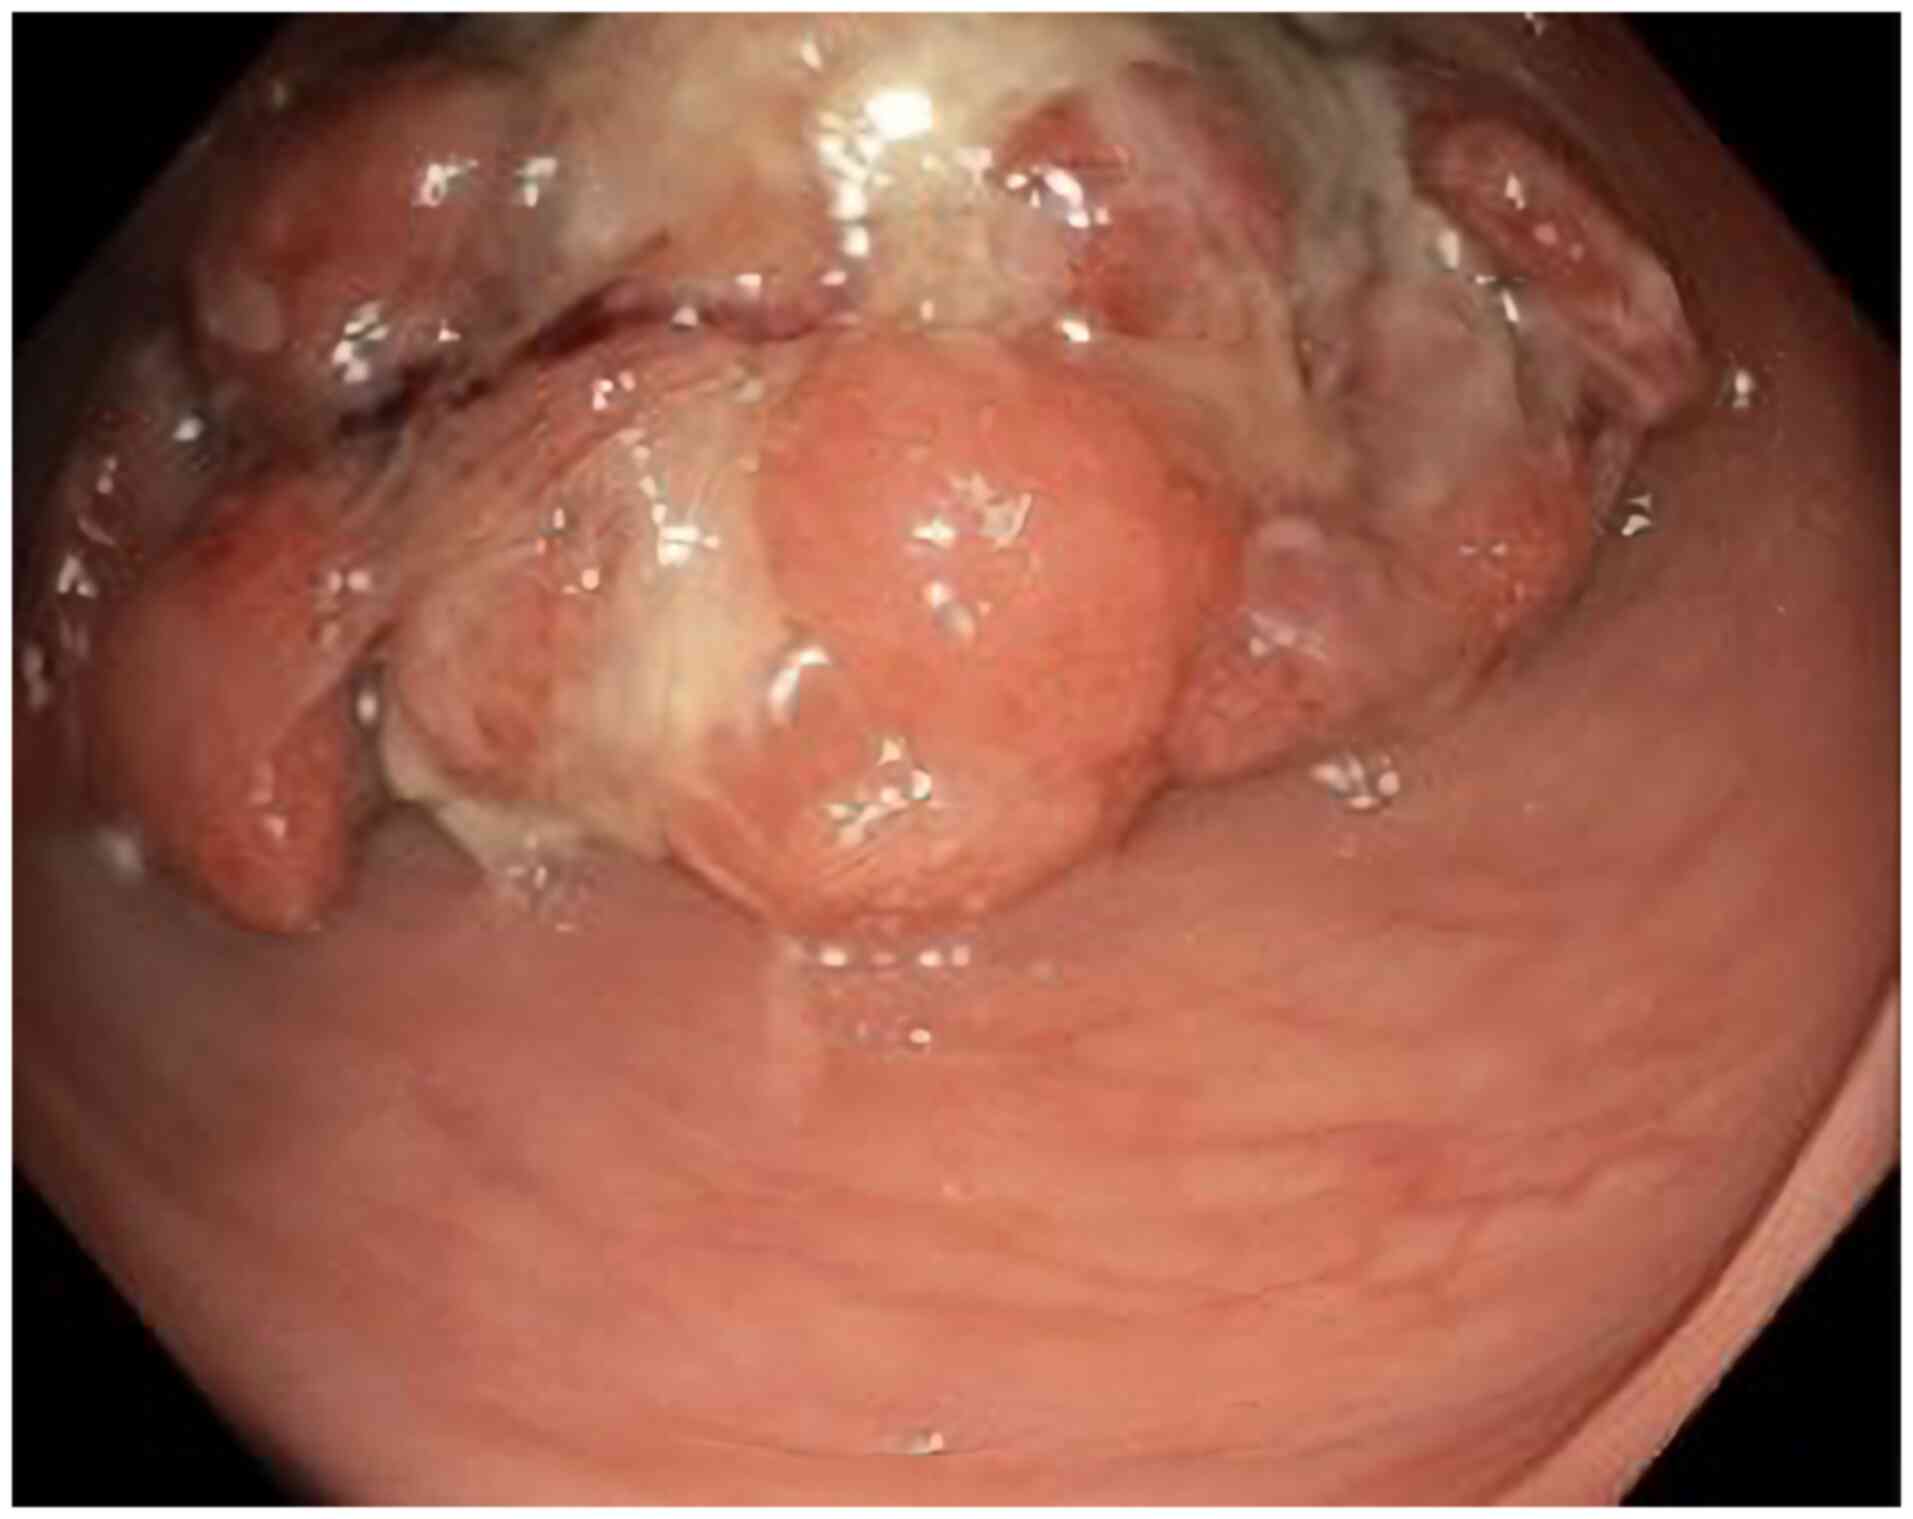

A superior digestive endoscopy did not reveal notable abnormalities. However, an inferior digestive endoscopy revealed a pedunculated polyp, which was biopsied for further examination (Fig. 2). The sample was first fixed in 10% neutral buffered formaldehyde, at room temperature for 24-48 h. Following fixation, the sample was embedded in paraffin and serial sections were cut at a thickness of 4 µm. The sections were stained with hematoxylin at room temperature for 5 min, followed by eosin for 2 min. The stained sections were examined under a light microscope at varying magnifications, in this case 20 and 40x. Histopathological examination revealed an adenomatous polyp with areas of moderately differentiated adenocarcinoma that did not involve the muscularis mucosae layer (Fig. 3, Fig. 4 and Fig. 5).

Figure 2

Pediculate polyp identified in inferior digestive endoscopy.

An inferior digestive endoscopy revealed a pedunculated polyp in the descending colon and an endoscopic polypectomy was subsequently performed. Histopathological examination confirmed the presence of a malignant polyp with areas of moderately differentiated adenocarcinoma infiltrating the submucosal layer, as well as regions classified as carcinoma in situ not extending beyond the muscularis mucosae layer (Fig. 3).